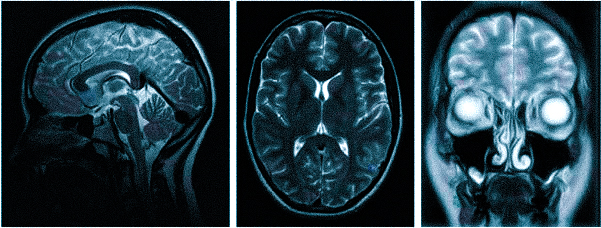

МРТ при головных болях (в трех проекциях) позволяет получить объемные изображения, что помогает выявить даже незначительные изменения и отличить патологию от нормы.

- МРТ (магнитно-резонансная томография) — процедура, которая предоставляет полное представление о состоянии исследуемой области и о наличии заболеваний. Снимки получаются благодаря воздействию магнитного поля на организм.

Для процедуры пациент ложится на стол-транспортер, который заезжает в томограф — сканирующее устройство. На время обследования пациент находится в трубе и должен оставаться неподвижным для получения четкого изображения. Процедура занимает от 15 минут.